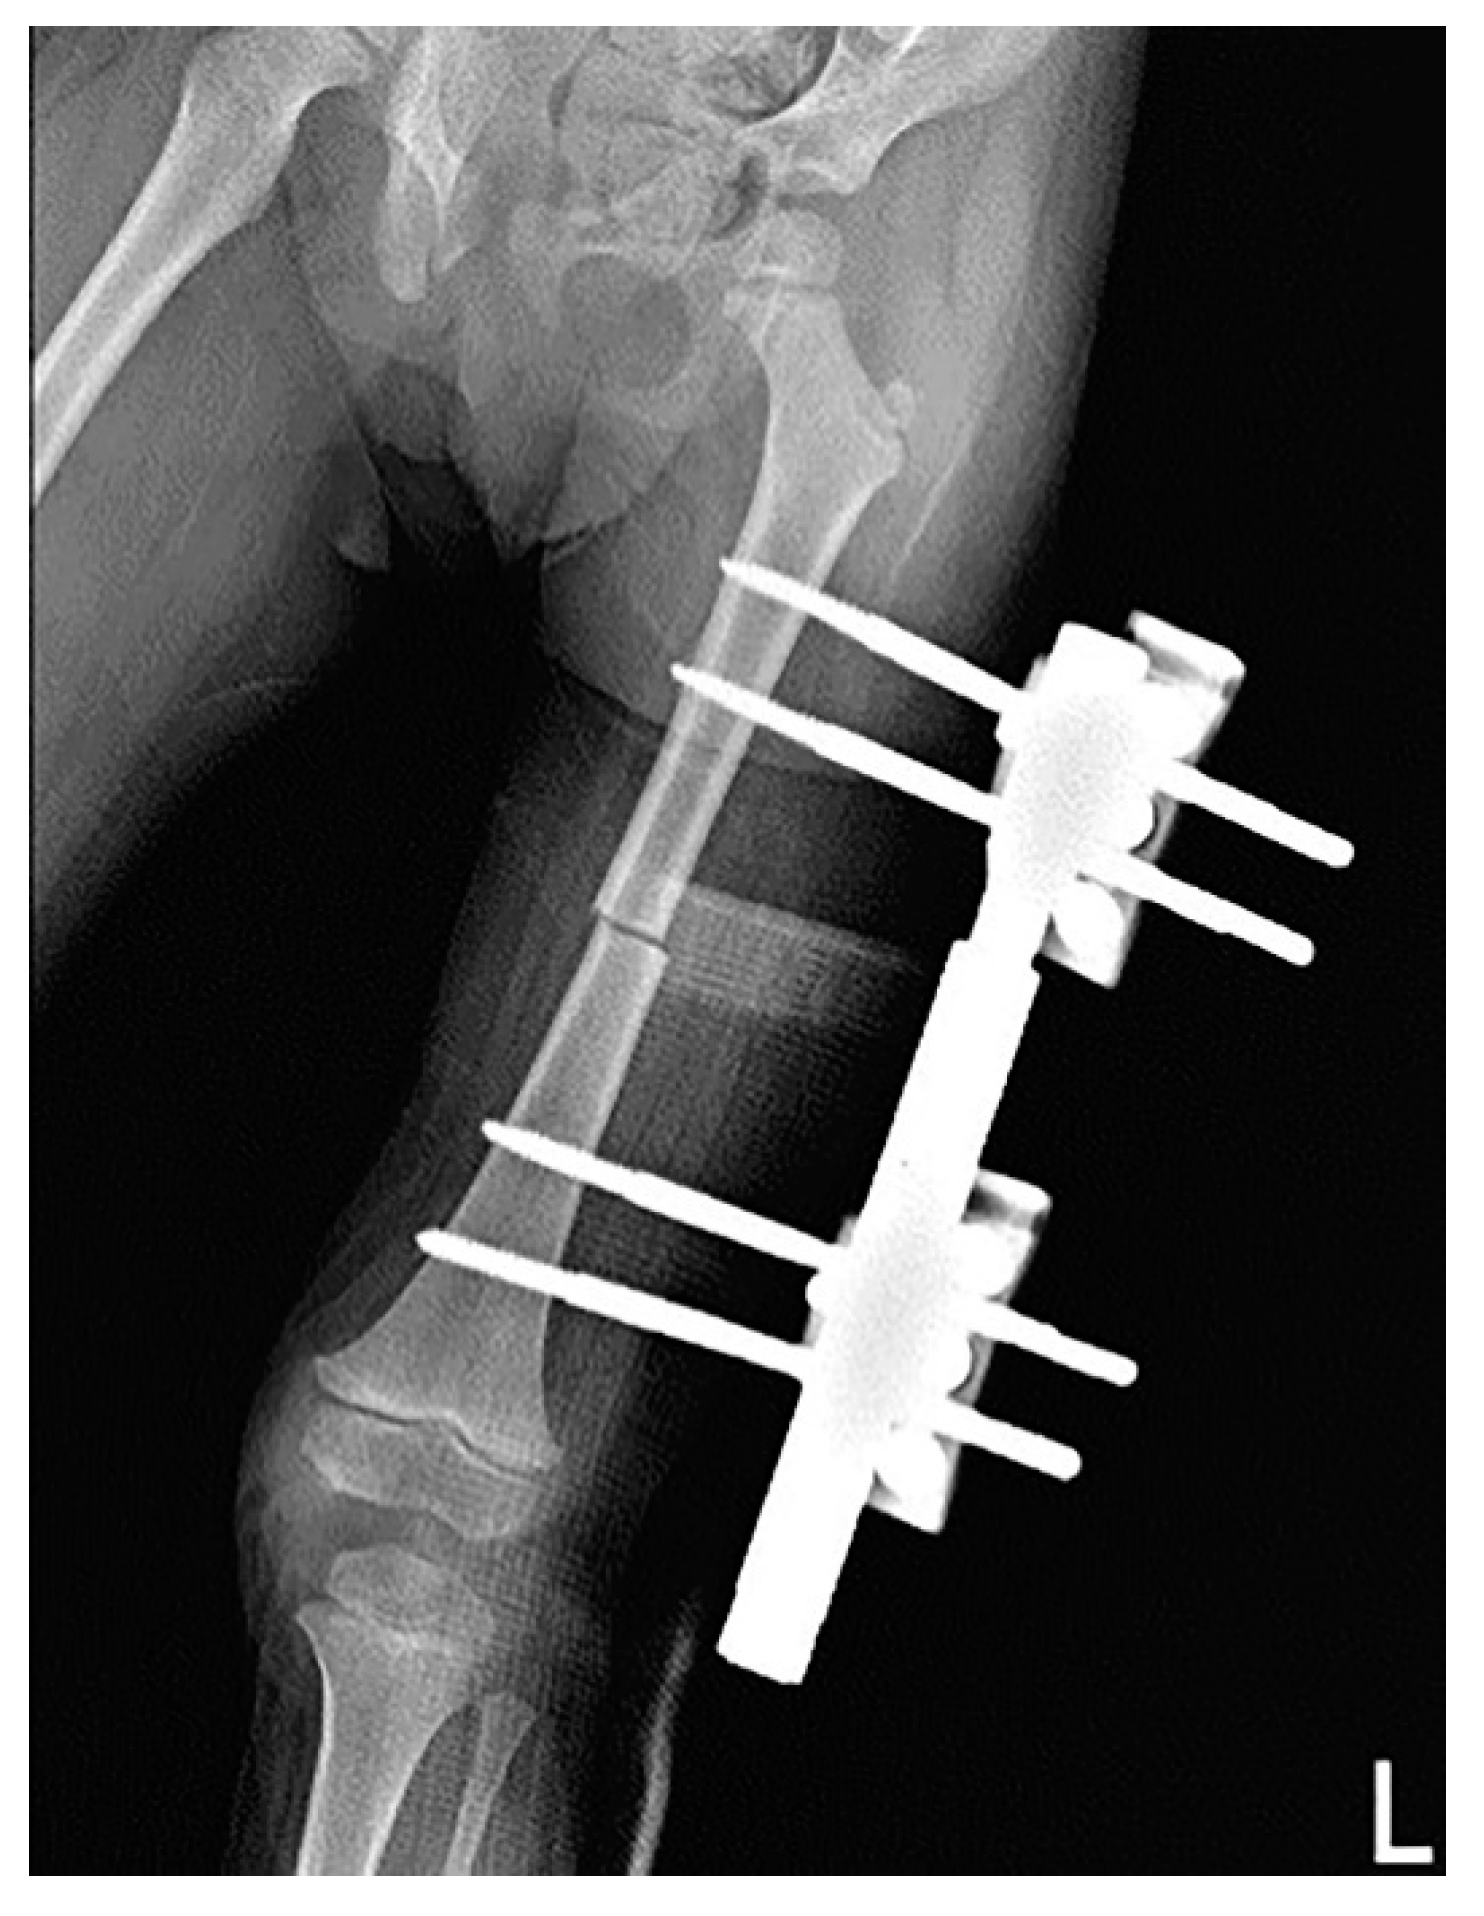

2. Case Description